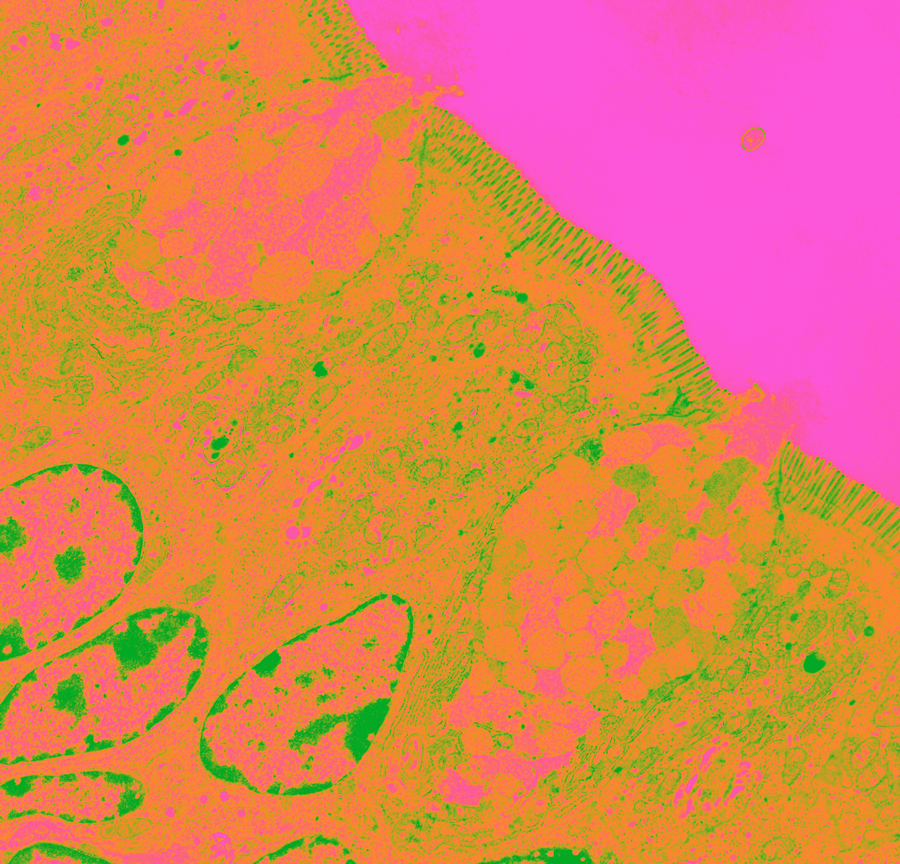

Goblet cell